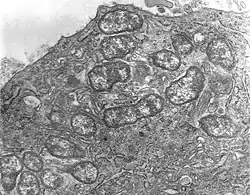

Orientia tsutsugamushi is a mite-borne bacterium belonging to the family Rickettsiaceae and is responsible for the disease scrub typhus in humans. It is an obligate intracellular parasite of trombiculid mites, in which natural transmission is maintained from the female to its eggs (transovarial transmission) and from the eggs to adults (transstadial transmission). With a genome of only 2.0–2.7 Mb, it has the most repeated DNA sequences among bacteria. It is transmitted by mite larvae (chiggers) from rodents, the natural hosts of mites, to humans through accidental bites. Naosuke Hayashi first described it in 1920, giving it the name Theileria tsutsugamushi, but it was renamed to Orientia tsutsugamushi in 1995, owing to its unique properties. Unlike other Gram-negative bacteria, its cell wall lacks lipophosphoglycan and peptidoglycan. It instead has a unique 56-kDa type-specific antigen (TSA56), which gives rise to many strains (sub-types) of the bacterium such as Karp, Gilliam, Kato, Shimokoshi, Kuroki, and Kawasaki. It is most closely related to Candidatus Orientia chuto, a species described in 2010. Primarily indicated by undifferentiated febrile illnesses, the infection can be complicated and often fatal. Diagnosis is difficult and requires laborious detection methods such as the Weil–Felix test, rapid immunochromatographic test, immunofluorescence assays, ELISA, or PCR. Eschar, if present on the skin, is a good diagnostic indicator. One million infections are estimated to occur annually in the endemic region called the Tsutsugamushi Triangle, which covers the Russian Far East in the north, Japan in the east, northern Australia in the south, and Afghanistan in the west. However, infections have also spread to Africa, Europe and South America. Antibiotics such as azithromycin and doxycycline are the main prescription drugs. There is no vaccine for the infection.